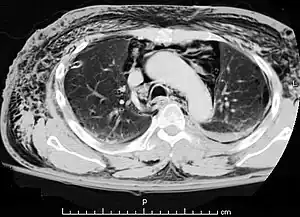

A CT scan showing air in the mediastinum with subcutaneous emphysema, which can result in Hamman's syndrome

Hamman's syndrome, also known as Macklin's syndrome, is a syndrome of spontaneous subcutaneous emphysema[1] (air in the subcutaneous tissues of the skin) and pneumomediastinum (air in the mediastinum, the center of the chest cavity), sometimes associated with pain and, less commonly, dyspnea (difficulty breathing), dysphonia, and a low-grade fever.